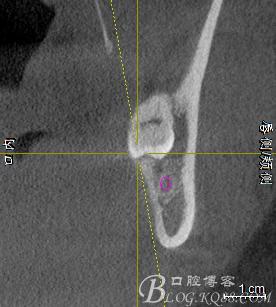

口內(nèi):38未萌出。37遠中牙周袋10mm,CT:38牙冠倒置。牙齦紅腫,捫診可有少量血性滲出,無波動感。印象診斷:38冠周炎。處理:1.抗炎治療,改善張口度。2.炎癥消退后,拔除38.

一、術(shù)前CBCT影像資料